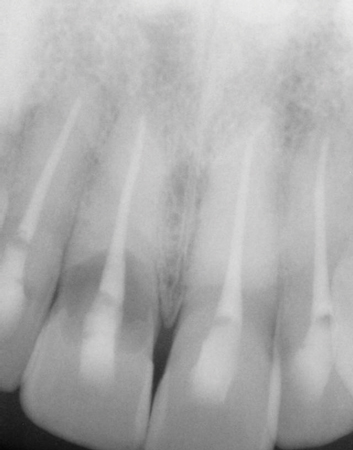

Figure 2: Prior to procedures, teeth appeared healthy with no clinical signs of trauma.

My periodontist looked at me and said my case would require an oral and maxillofacial surgeon to do a surgical extraction and that he could not place an implant for me. Argh. I love my periodontist, yet understand that this is why there are many different types of specialists. Clearly, with so little root left, this tooth was going to shatter imminently if not certainly during the extraction process. My general dentist then informed me that she, too, would prefer I see a prosthodontist as this was going to potentially change my entire smile. I was now dealing with a full bag of emotions, meeting a new team for restoration (see Figure 2).